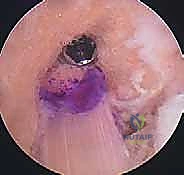

الخطوة الأولى: الفحص بالمنظار الجراحي 4K

يستخدم الدكتور